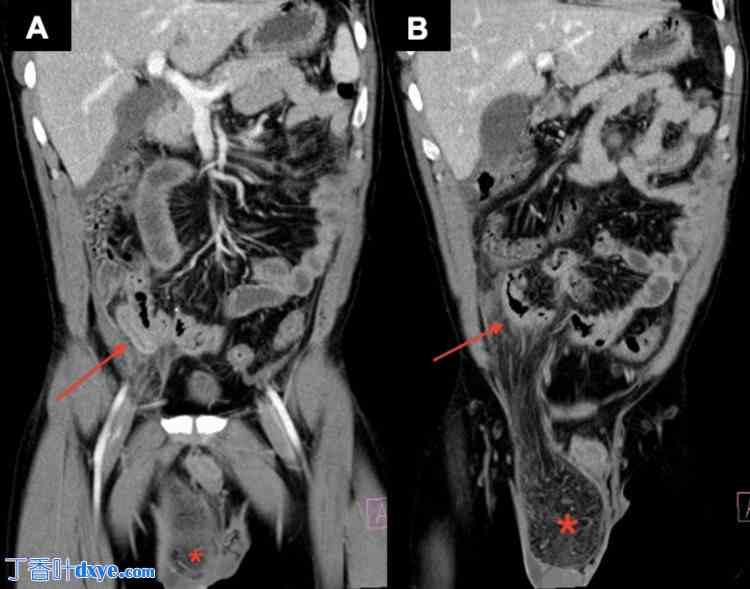

腹部和盆腔计算机断层扫描 (CT) 显示右侧腹股沟疝,疝内含脂肪,阑尾增大且发炎,并突入疝囊,同时可见腔外气体、少量腹水、腹膜炎症改变以及弥漫性肠管增厚(图 1 和图 2)。

图 1. 腹部和盆腔冠状位 (A 和 B) CT 图像,静脉注射造影剂后显示右侧阿米安疝 (Amyand's hernia),并伴有阑尾炎穿孔。

X 射线影像显示阑尾发炎(红色箭头)并突入疝囊(红色星号)。

CT:计算机断层扫描